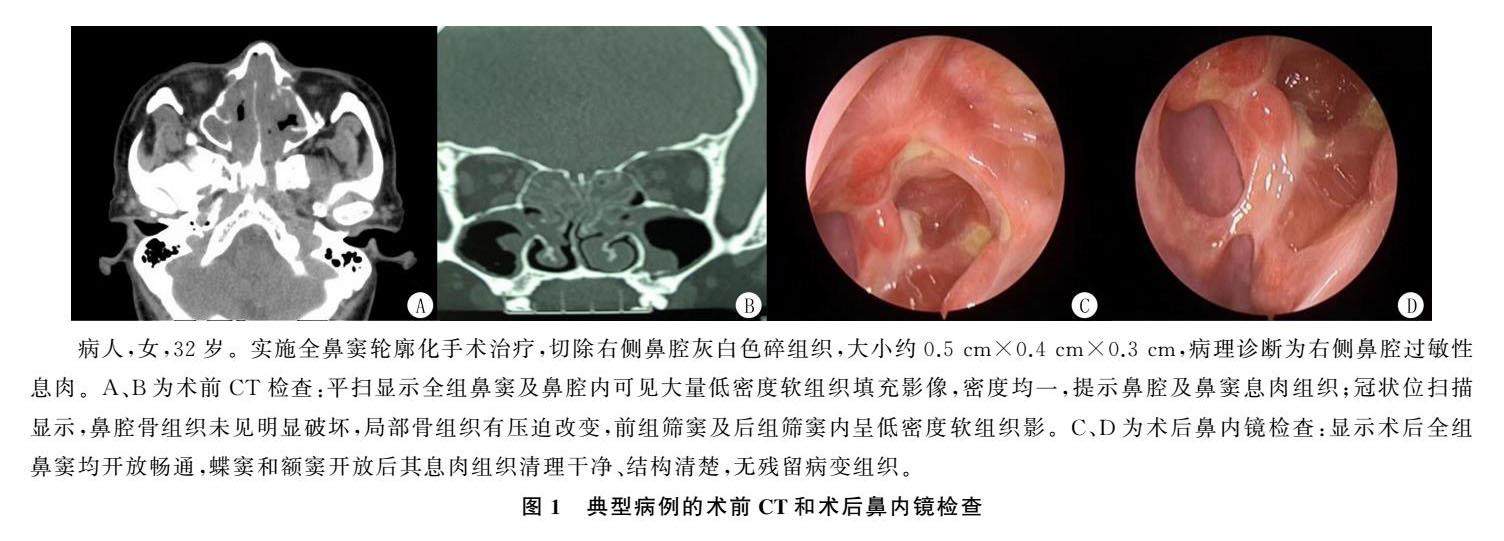

论著 | 两种手术方式对Eos型慢性鼻窦炎伴鼻息肉病人疗效及安全性评价

论著 | 两种手术方式对Eos型慢性鼻窦炎伴鼻息肉病人疗效及安全性评价